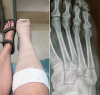

ALL ACCESS extends well-wishes to Q PRIME SOUTH VP/Country Promotion ANGELA LANGE, who is on the mend after breaking her foot while on vacation. LANGE told ALL ACCESS she broke a bone on the outward-facing side of her right foot when she missed a step and rolled her ankle in the wrong direction.

"Not how I planned my vacation!" shared LANGE via FACEBOOK. "Broken foot and possible surgery when I get home. Does this girl know how to have a good time, or what?" Send your get-well-wishes to LANGE here.